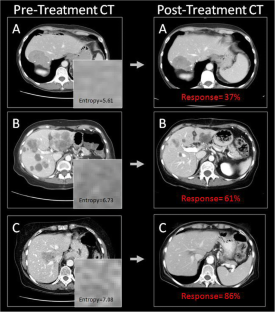

• Heterogeneity and enhancement patterns of CRLM can be measured with quantitative imaging.

Fig. 1

Fig. 2

Fig. 3